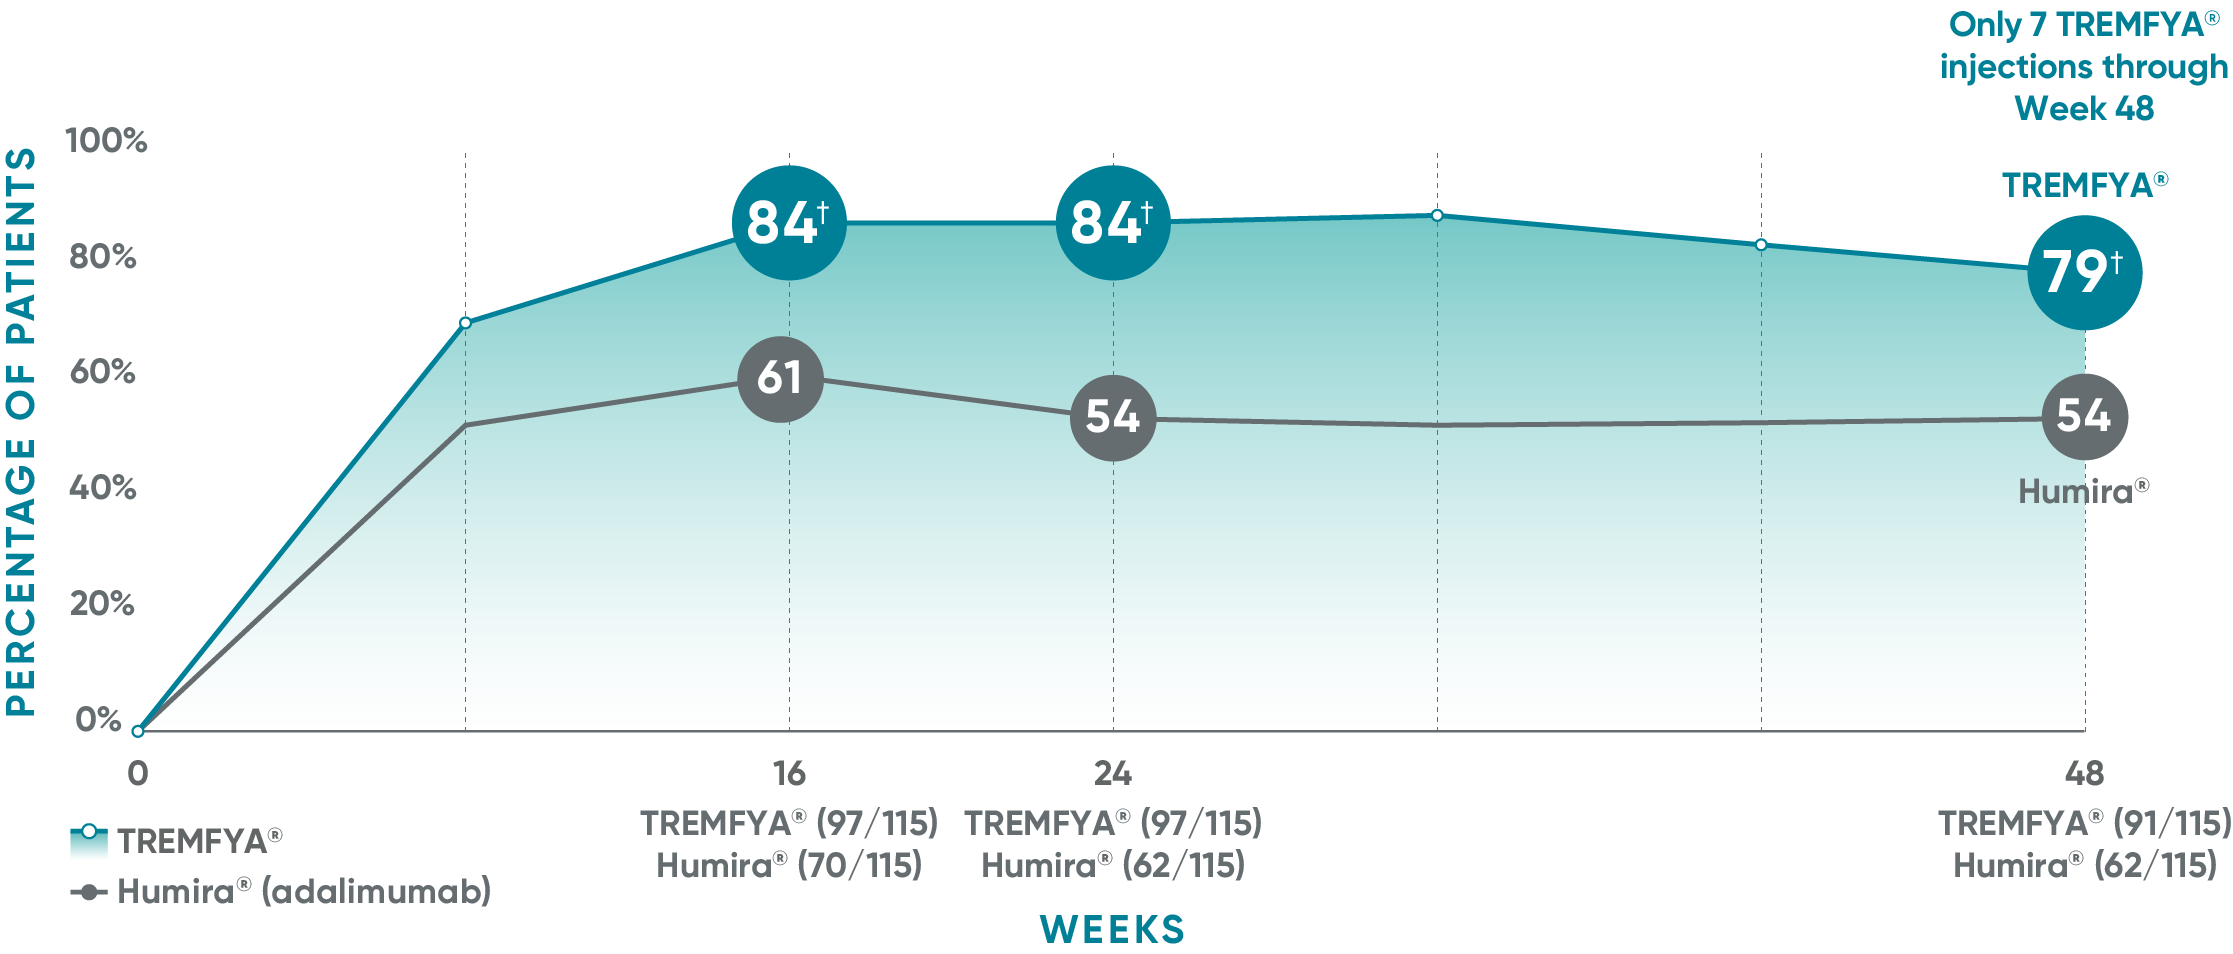

VOYAGE 1: Major secondary endpoints PASI 90 response at Weeks 16, 24, and 48 (NRI)*

The same patients may not have responded at each time point.

VOYAGE co-primary endpoints at Week 16 (NRI)1,2:

VOYAGE 1—PASI 90: TREMFYA® 73% (241/329), placebo 3% (5/174) (P<0.001). IGA 0/1: TREMFYA® 85% (280/329), placebo 7% (12/174) (P<0.001). VOYAGE 2—PASI 90: TREMFYA® 70% (347/496), placebo 2% (6/248) (P<0.001). IGA 0/1: TREMFYA® 84% (417/496), placebo 8% (21/248) (P<0.001).

VOYAGE 2: Major secondary endpoint at Week 16 (NRI)1,2*†

- 64% (102/160) of patients receiving TREMFYA® achieved PASI 90 vs 42% (34/81) of patients receiving Humira®

VOYAGE 2: Major secondary endpoint at Week 24 (NRI)1,2*‡

- 71% (113/160) of patients receiving TREMFYA® achieved PASI 90 vs 51% (41/81) of patients receiving Humira®

*Results from North American sites only, which used US-licensed Humira®.

†P<0.001 vs Humira®.

‡P=0.003 vs Humira®.

Humira is a registered trademark of Abbvie Biotechnology Ltd. Corporation.

NRI=nonresponder imputation.